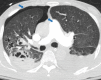

The coronavirus disease 2019 (COVID-19) pandemic is a global health care emergency. Although reverse-transcription polymerase chain reaction testing is the reference standard method to identify patients with COVID-19 infection, chest radiography and CT play a vital role in the detection and management of these patients. Prediction models for COVID-19 imaging are rapidly being developed to support medical decision making. However, inadequate availability of a diverse annotated data set has limited the performance and generalizability of existing models. To address this unmet need, the RSNA and Society of Thoracic Radiology collaborated to develop the RSNA International COVID-19 Open Radiology Database (RICORD). This database is the first multi-institutional, multinational, expert-annotated COVID-19 imaging data set. It is made freely available to the machine learning community as a research and educational resource for COVID-19 chest imaging. Pixel-level volumetric segmentation with clinical annotations was performed by thoracic radiology subspecialists for all COVID-19-positive thoracic CT scans. The labeling schema was coordinated with other international consensus panels and COVID-19 data annotation efforts, the European Society of Medical Imaging Informatics, the American College of Radiology, and the American Association of Physicists in Medicine. Study-level COVID-19 classification labels for chest radiographs were annotated by three radiologists, with majority vote adjudication by board-certified radiologists. RICORD consists of 240 thoracic CT scans and 1000 chest radiographs contributed from four international sites. It is anticipated that RICORD will ideally lead to prediction models that can demonstrate sustained performance across populations and health care systems.